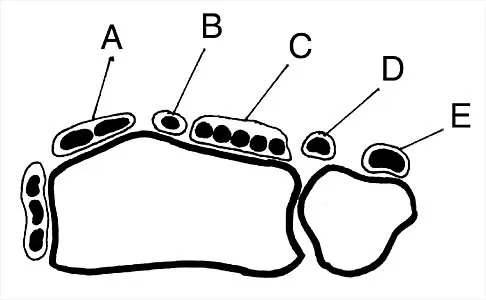

Figure 30 shows an axial cross section of extensor tendon anatomy in zone 7 of the wrist. What letter best depicts the location of the posterior interosseous nerve?

Explanation

The posterior interosseous nerve in contained in the floor of the fourth dorsal compartment of the wrist, which is labelled C in this diagram. Tubiana R, McCullough CJ, Masquelet AC: An Atlas of Surgical Exposures of the Upper Extremity. Philadelphia, PA, JB Lippincott, 1990, p 224.

References:

- Hollinshead WH: Anatomy for Surgeons: The Back and Limbs, ed 3. Philadelphia, PA, Harper and Row, 1982, p 430.